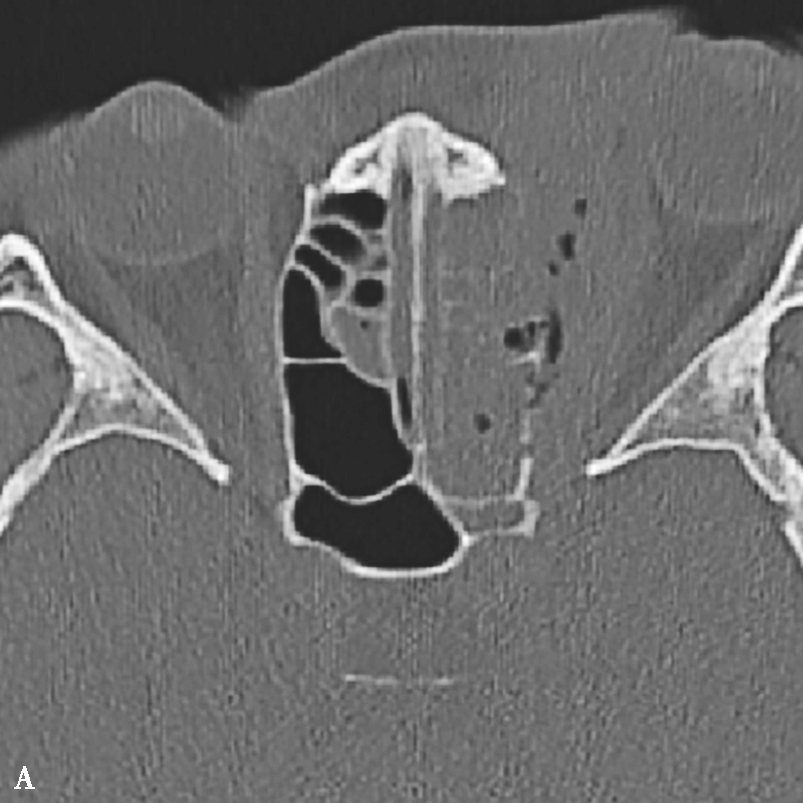

1.CT表现

该病息肉样变及水肿通常发生于中鼻甲周围,即病变大多位于前组筛窦、后组筛窦以及嗅裂区,表现为以筛窦为主的高密度影。呈典型的“双重密度”表现,即受累鼻窦腔内斑片状或云雾状高密度影,其中高密度影对应嗜酸性黏蛋白(eosinophilic mucin,EM)的位置,周围低密度影为水肿的鼻窦黏膜(图1-3-24A、B)。

2.MRI表现

EM表现为T 1 低信号或中等信号,T 2 极低信号或信号缺失(图1-3-24C~E)。

图1-3-24 嗜酸细胞增多黏液性鼻窦炎

A、B.横断面及冠状面CT骨窗,示双侧额窦、筛窦、上颌窦及蝶窦腔充填软组织影,密度不均匀,见多发斑片状磨玻璃样密度影“双重密度影”;双侧中、总鼻道见软组织影充填;C~E.横断面T 1 WI、T 2 WI及冠状面T 1 WI,示全组鼻窦窦腔充填长T 1 、混杂短到长T 2 信号影,双侧中鼻道、总鼻道及上颌窦窦口区可见小斑片状略短T 1 混杂等到短T 2 信号影